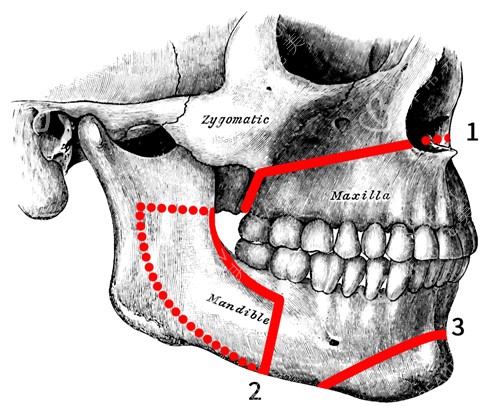

正颌手术是一种复杂的医疗美容手术,旨在通过调整颌骨的位置和形态,改善面部轮廓和咬合功能。

医院在正颌手术方面采用了特有的delaire头影测量分析技术,这项技术能够精细测量和分析患者的头颅结构,为手术方案的制定提供科学依据。

此外,医院还引进了3D头颅数字化技术,能够在手术前对患者的头颅进行三维重建,实现手术过程的可视化,提高手术的精细度和可靠性。

与传统的正颌手术相比,重庆松山整形医院采用的技术能够缩短手术时间周期,患者无需经过长时间的术前正畸咬合调整,可直接进行手术。